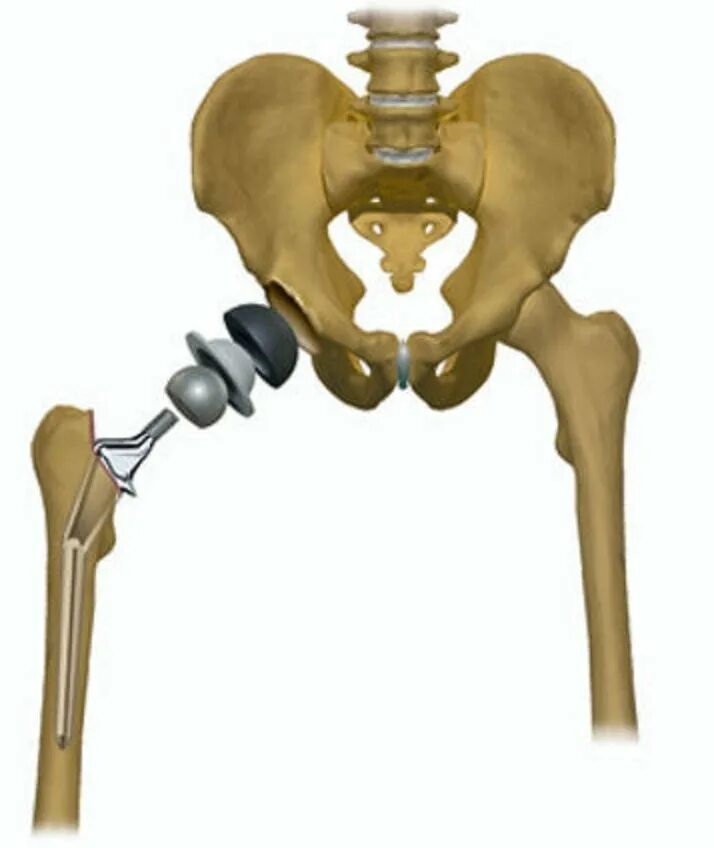

Тазобедренный сустав 3 степени лечение